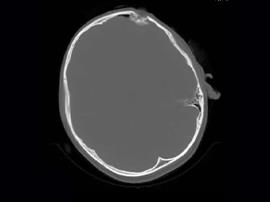

کد خبر : 191471 تاریخ : 1404/08/25 12:15:14 در بیمارستان امیرالمؤمنین (ع) گناوه صورت گرفت؛ جراحی موفقیتآمیز کودک ۱۰ ساله پس از فرو رفتن چوب در سر پیغام: سرپرست بیمارستان امیرالمؤمنین (ع) گناوه از انجام عمل جراحی موفق یک کودک ۱۰ ساله، به دنبال فرورفتگی جسم چوبی در ناحبه چپ جمجمه که با خونریزی مغزی و کاهش سطح هوشیاری همراه بود، در این مرکز خبر داد. به گزارش پیغام به نقل از روابط عمومی بیمارستان امیرالمؤمنین (ع) گناوه، منوره نصیری خورموجی با اشاره به محل حادثه گفت: متأسفانه این فرورفتگی دقیقاً در ناحیه چپ جمجمه رخ داده بود و از لحاظ جراحی، منطقهای بسیار حساس محسوب میشود که با وجود خونریزی مغزی و کاهش سطح هوشیاری، تیم جراحی این مرکز با مسئولیت متخصص جراحی مغز و اعصاب و ستون فقرات دکتر محمد محمدپور، بلافاصله وارد عمل شد. سرپرست بیمارستان امیرالمؤمنین (ع) گناوه ضمن تشکر از کادر پزشکی و کارکنان اتاق عمل بیمارستان خاطرنشان کرد: طی دو سال گذشته، شاهد انجام اعمال جراحی موفق بیشماری در حوزه تخصصی مغز و ستون فقرات در همین اتاق عمل بودهایم که این موفقیتها نتیجه دانش، تجربه و حس تعهد تیم ماست و تأکید میکنیم تا آنجا که در توان داریم همچنان به خدمترسانی به هموطنان و همشهریان عزیز ادامه خواهیم داد. جراح مغز و اعصاب و ستون فقرات بیمارستان امیرالمؤمنین (ع) نیز اظهار داشت: ما یک عمل جراحی ۴ ساعته، را برای خارجسازی دقیق جسم خارجی، ترمیم ساختارهای آسیبدیده مغز و بازسازی جمجمه و همچنین ترمیم عصب انجام دادیم. بعد از انجام عمل جراحی، بیمار به بخش مراقبتهای ویژه آی.سی.یو منتقل شد و پس از گذشت ۸ ساعت، بیمار کاملاً هوشیار شد، از دستگاههای حمایتی تنفسی جدا گردید و توانست بدون مشکل غذا مصرف کند که این نشاندهنده سلامت اولیه پاسخ مغز به جراحی بود. محمد محمدپور در تشریح موفقیت جراحی این کودک ۱۰ ساله و ادامه درمان عنوان کرد: سیتیاسکن نهایی انجام شد، بیمار با حال عمومی رضایتبخش و هوشیاری کامل، جهت ادامه درمان به بخش عمومی منتقل شد که ظرف ۲۴ ساعت آینده ترخیص خواهد شد. منبع: پایگاه خبری تحلیلی پیغام لینک مستقیم : http://peigham.ir/shownews.aspx?id=191471